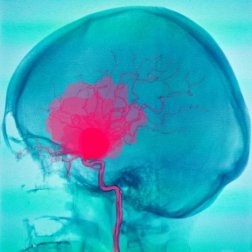

Emorragia subdurale e subaracnoidea

In un’emorragia subdurale o subaracnoidea, il primo evento è il deflusso di sangue dai vasi sanguigni che va ad accumularsi negli spazi tra le meningi. Questo causa danni al tessuto cerebrale, con quadri clinici di diverso tipo.

Tuttavia, a seconda che l’emorragia sia subdurale o subaracnoidea, gli elementi scatenanti e il decorso della malattia saranno diversi.